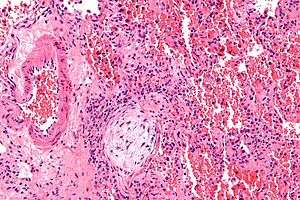

Micrograph showing a Masson body (off center left/bottom of the image – pale circular and paucicellular), as may be seen in bronchiolitis obliterans organizing pneumonia. The Masson body plugs the airway. The artery associated with the obliterated airway is also seen (far left of the image). H&E stain. | |

Pulmonary physiology is restrictive with a reduced diffusion capacity of the lung for carbon monoxide (DLCO). Airflow limitation is uncommon; gas exchange is usually abnormal and mild hypoxemia is common. Bronchoscopy with bronchoalveolar lavage reveals up to 40% lymphocytes, along with more subtle increases in neutrophils and eosinophils. In patients with typical clinical and radiographic features, a transbronchial biopsy that shows the pathologic pattern of organizing pneumonia and lacks features of an alternative diagnosis is adequate to make a tentative diagnosis and start therapy. On surgical lung biopsy, the histopathologic pattern is organizing pneumonia with preserved lung architecture; this pattern is not exclusive to BOOP and must be interpreted in the clinical context.

Histologically, cryptogenic organizing pneumonia is characterized by the presence of polypoid plugs of loose organizing connective tissue (Masson bodies) within alveolar ducts, alveoli, and bronchioles.